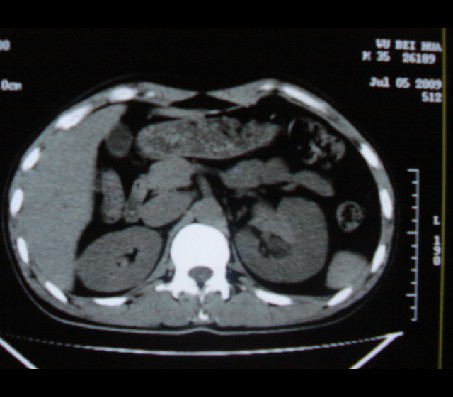

标题: CT20935:左肾占位,请会诊!

男性,35岁,ct号26189,左侧腰痛并血尿一天入院。

左肾癌侵犯肾盂可能性大,建议增强.

考虑左肾癌可能性大,建议增强扫描。

左肾癌侵犯肾盂可能性大。

肾癌侵犯肾盂,肾盂出血,肾盂内为血肿

首先考虑恶性肿瘤性病变,考虑左肾癌可能性大,建议增强扫描。